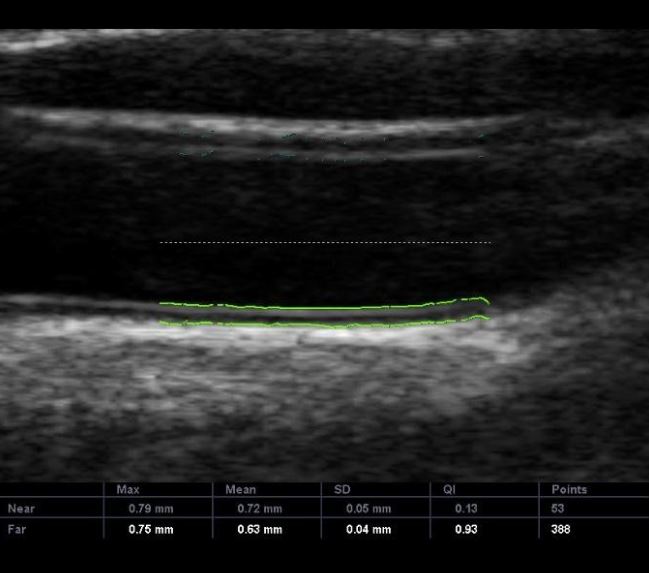

Medida da espessura mediointimal

O Doppler de carótidas e vertebrais permite a medida da espessura da parede da artéria, ou seja, a espessura mediointimal.

Quando a medida da espessura mediointimal da artéria carótida comum estiver acima do percentil 75 para sexo, raça e idade, a pessoa encontra-se no grupo de risco e modificações no estilo de vida e medicações podem ser implementadas para a prevenção.

Doppler de carótidas e vertebrais. Exemplo da medida da espessura mediointimal na artéria carótida comum.